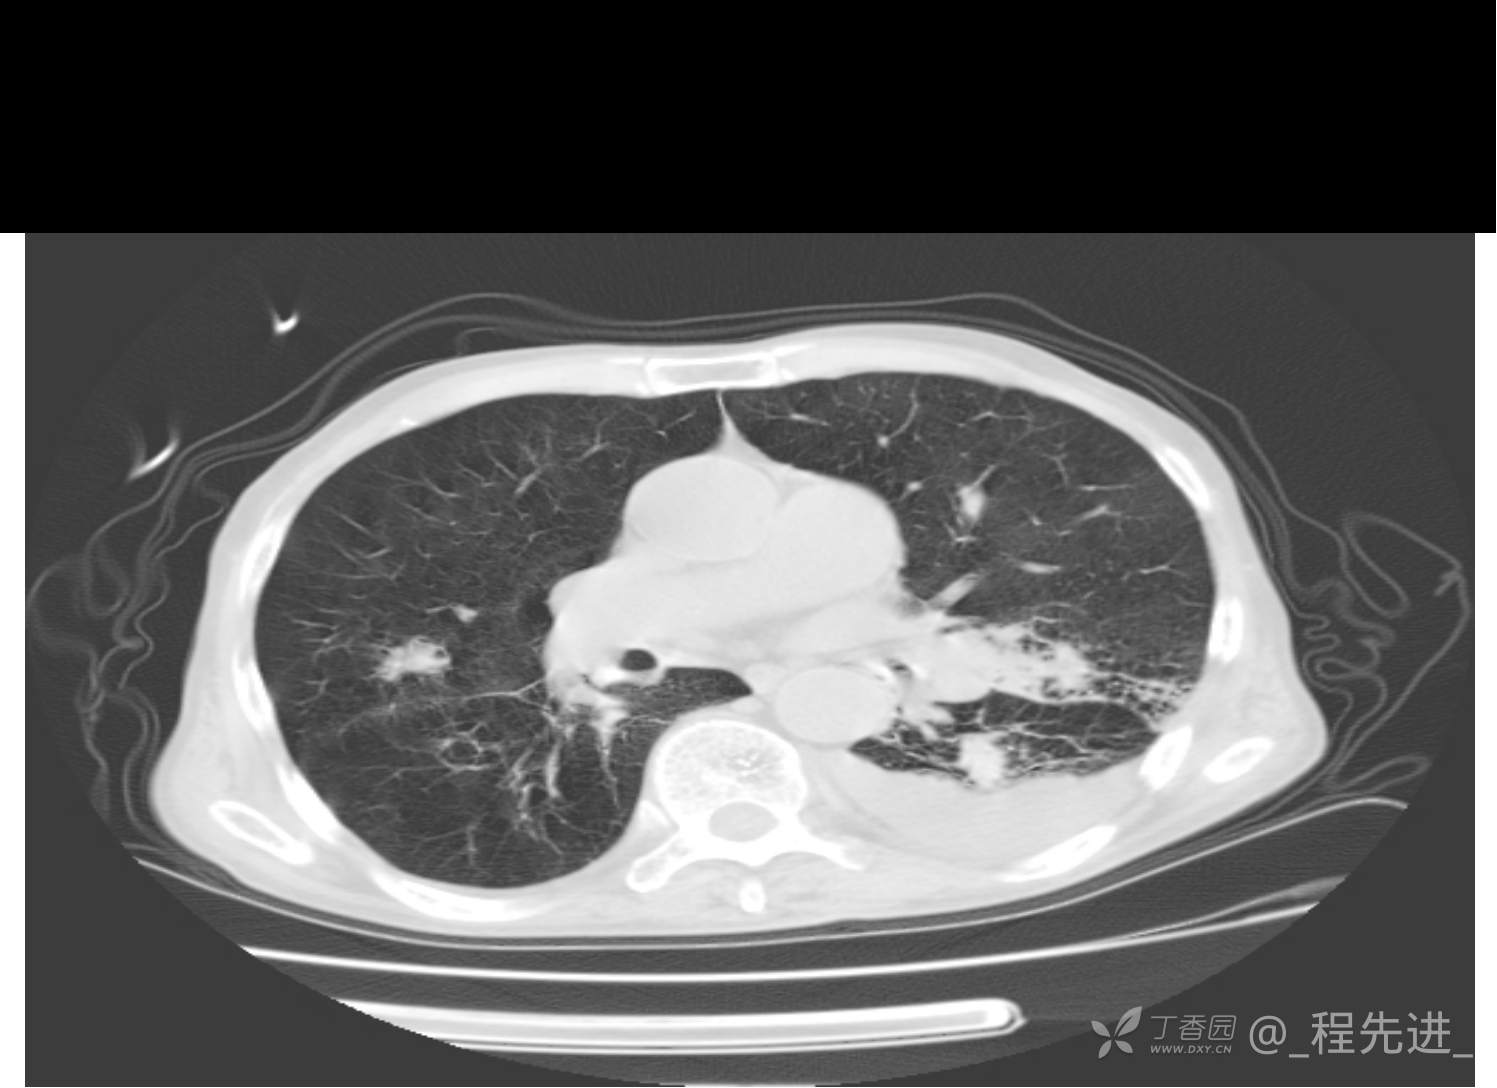

患者性别:男

患者年龄:81岁

简要病史:反复咳嗽、咳痰20余年,加重1周。两肺呼吸音低,可闻及散在干湿啰音。